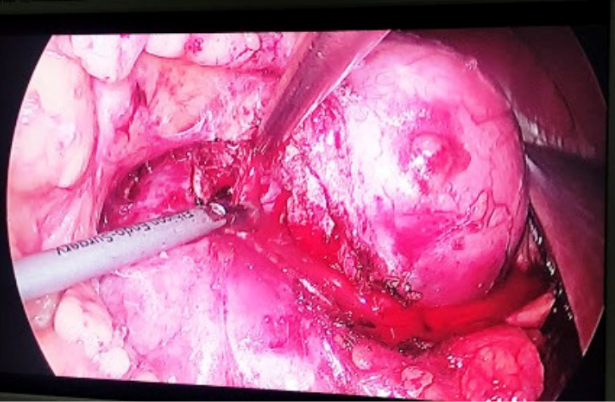

Con estos resultados, de decide programar cirugía para extracción del tumor renal derecho, al ser el paciente monorreno, se tiene como mejor opción quirúrgica la nefrectomía parcial derecha laparoscópica, se hace el cálculo de dificultad técnica mediante la escala RENAL Score, obteniendo un puntaje de 10ah, lo que nos marca una cirugía de alta complejidad, con riesgo de tener la necesidad de realizar una nefrectomía radical por la alta complejidad del procedimiento, se comenta con el paciente y se decide proceder con la cirugía preservadora de nefronas mediante nefrectomía parcial por abordaje laparoscópico.

La cirugía se realizó en posición de Israel Bergman izquierda, colocación de sonda Foley 16 Fr, se procede a colocar tres trocares de trabajo: a nivel paraumbilical de 10 mm y otro de 10 mm a nivel de línea clavicular media a dos centrimetros de la cresta iliaca antero-superior, otro de 5 mm en línea media clavicular a nivel subcostal (Figura 2). Se liberan adherencias, se incide fascia de Told, se diseca y separa colon, se accede a retroperitoneo, se identificó el uréter y se disecó en sentido cefálico, se localizó hilio renal, el cual se diseco en su totalidad, con el objetivo de tener un buen control vascular en caso necesario, se procedió a disecar grasa perirrenal, se localiza tumor renal, se limpia borde del tumor, y se procede a incidir capsula renal a nivel del borde renal, con un margen de 1 cm del borde visible, se realizar corte de parénquima renal con energía bipolar, se procede a seccionar por completo el tumor, se realiza el procedimiento sin isquemia, (Figura 3) se cauteriza lecho quirúrgico, se procede a cierre de colectores con Vicryl 2-0, surgete continuo, en plano profundo, se coloca Gelfoam hemostático en lecho quirúrgico, y se afronta bordes de parénquima renal con crómico 1, se corrobora adecuada hemostasia, se procede a dejar drenaje en lecho, y se extrae pieza quirúrgica, se realiza el procedimiento sin complicaciones, con un sangrado estimado de 300 ml, se deja al paciente en reposo absoluto, y con control de la función renal, se observa ligera elevación de la creatinina a las 24 hrs, llegando a 2 mg/dL, sin necesitar apoyo dialítico, con posterior recuperación de la función renal a niveles basales a las 72 hrs de la cirugía.